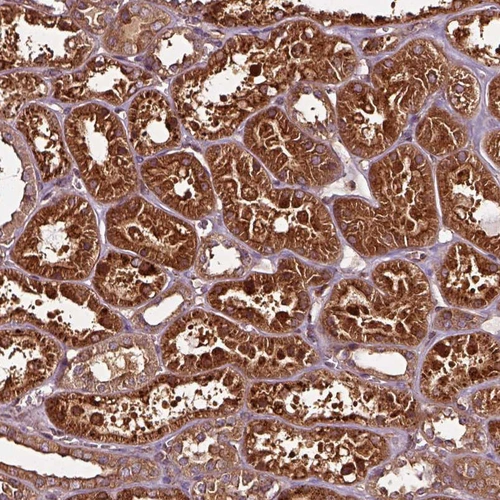

Immunohistochemical staining of human rectum shows strong cytoplasmic granular positivity in glandular cells.